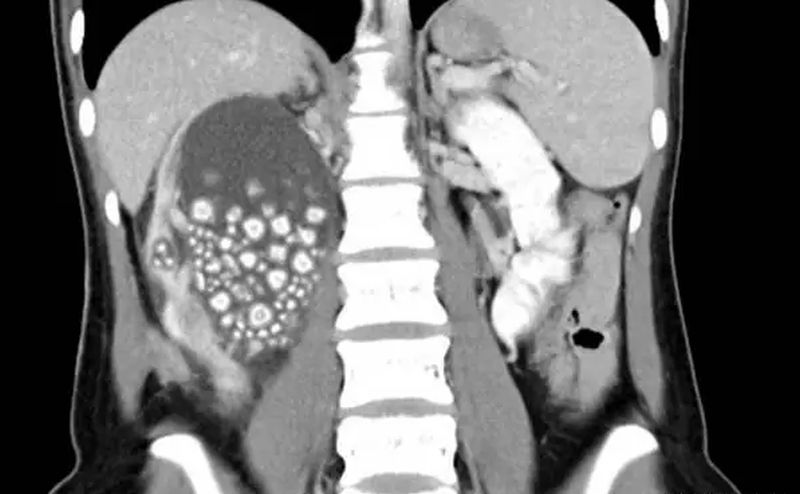

Djevojci uklonjeno 300 kamenčića iz bubrega FOTO

17.12.2023. | 18:58Jedna 20-godišnja djevojka sa Tajvana nedavno je podvrgnuta operaciji u kojoj su ljekari uklonili 300 kamenćića iz bubrega!.